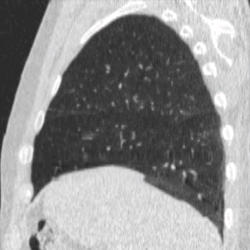

Four-dimensional computed tomography (4DCT) is a type of CT scanning which records multiple images over time. It allows playback of the scan as a video, so that physiological processes can be observed and internal movement can be tracked. The name is derived from the addition of time (as the fourth dimension) to traditional 3D computed tomography. Alternatively, the phase of a particular process, such as respiration, may be considered the fourth dimension.[1]

To minimise physical movements of the patient, some sort of immobilisation is typically used. To overcome physiological motion, such as breathing, 4DCT acquires images at a range of times and positions, allowing the extent of motion to be visualised (e.g. from maximum inspiration to maximum exhalation). The treatment plan can then be designed with a knowledge of the full range of possible positions of important organs, and the tumour (target) itself.[8]